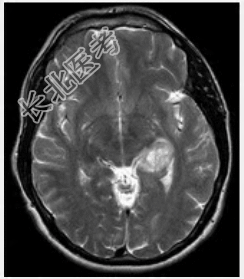

- 单项选择题下列哪项符合胶质母细胞瘤(如图所示)的特点

A、以额叶最多见

B、血运不丰富

C、周围水肿不明显

D、位于大脑半球灰质内

E、主要发生于儿童